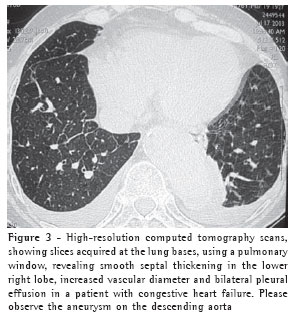

The thickening of the interlobular septa was bilateral in thirteen cases (Figures 1-4) and unilateral in two, also in the patients with fibrosing mediastinitis. In all cases, the thickening was of the smooth type.

Pleural effusion was the third most common tomographic finding overall and was the most common nonparenchymal finding, being found in 13 patients (87%), predominantly in the bilateral form (n = 11) (Figures 1-3).

Among the eleven patients with bilateral pleural effusion, nine presented asymmetric pleural effusion, predominantly on the right side. Two cases of exclusively right-sided pleural effusion were identified.

Vascular diameter was increased in seven cases (44%) (Figure 3).